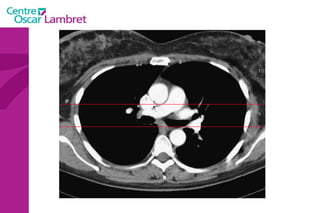

Le médiastin C'est l’espace au centre du thorax. Il est situé en avant de la colonne vertébrale et peut être divisé en plusieurs quadrants.  Il est divisé, par convention, en : médiastin postérieur :  contenant notamment  l’oesophage et l’aorte descendante.  médiastin moyen :  contenant les voies aériennes supérieures : trachée et sa division (carène).  médiastin antérieur :  contenant le cœur, l’aorte ascendante, les artères pulmonaires et la veine cave supérieure.

Le médiastin Le médiastin   antérieur  comprend : L’aorte ascendante Le tronc pulmonaire La veine cave supérieure Les cavités cardiaques sauf l’atrium gauche La loge thymique

Le médiastin Le  médiastin moyen  comprend : La trachée La carène Les pédicules pulmonaires : Les bronches souches Les veines et les artères pulmonaires Le segment horizontal de la crosse de l’aorte Le Tronc Artériel Brachio-Céphalique L’artère carotide primitive gauche La crosse de la grande veine azygos

Le médiastin Le médiastin  postérieur  comprend : Le canal thoracique La grande veine azygos et les veines hémi azygos L’œsophage L’aorte descendante et ses branches

L’appareil circulatoire L’ aorte  est la plus grande artère du corps.  Elle part du ventricule gauche du coeur et apporte notamment du sang oxygéné à toutes les parties du corps via la circulation. Elle est divisée en aorte thoracique et aorte abdominale. L’aorte thoracique  comprend trois segments : l'aorte ascendante, horizontale et descendante.

L’aorte ascendante  : L’aorte ascendante constitue le segment initial de l’aorte, elle fait 27 mm de diamètre et émerge du VG, dont elle est séparée par la valve aortique. Cette portion fait 6 cm de hauteur, divisé en deux régions: le sinus de Valsalva, fortement dilaté, oblique en avant.  le grand sinus aortique, dilaté, jusqu'à la portion horizontale de l’aorte.  L’appareil circulatoire

La  crosse de l’aorte  ou aorte horizontale :  L’aorte horizontale passe ensuite derrière l’artère pulmonaire et la bronche souche gauche. Trois vaisseaux naissent de cette crosse aortique: le tronc brachio-céphalique, l’artère carotide primitive gauche, et l’artère sous-clavière gauche. Ces vaisseaux irriguent la tête et les membres supérieurs. L’appareil circulatoire

L’aorte descendante  : L’aorte descend ensuite dans le médiastin, en arrière du cœur et en avant de l’oesophage dans sa partie supérieure, en arrière dans sa partie inférieure. Cette partie est relativement fixée par rapport aux deux autres segments. La jonction entre l’aorte horizontale et descendante est appelée isthme   aortique.  Elle traverse ensuite le diaphragme et devient l’aorte abdominale. L’appareil circulatoire